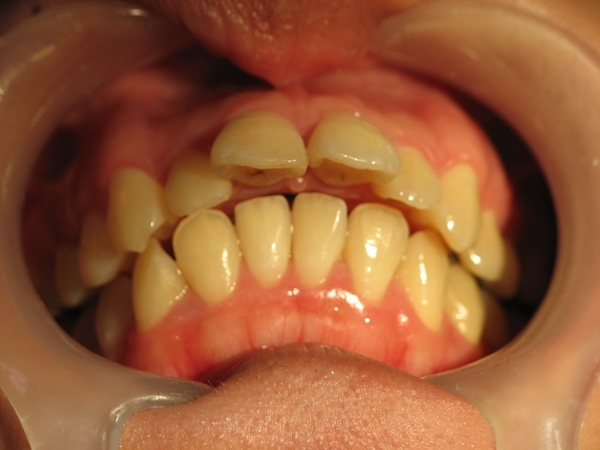

包含臉部照片、口內牙齒照片、X光照、側臉臉部分析圖,及口內牙齒取模,

除了暴牙的部分,張院長還說我門牙上有個小洞,

建議也可以一起關起來(放大細看後缺點一覽無遺),